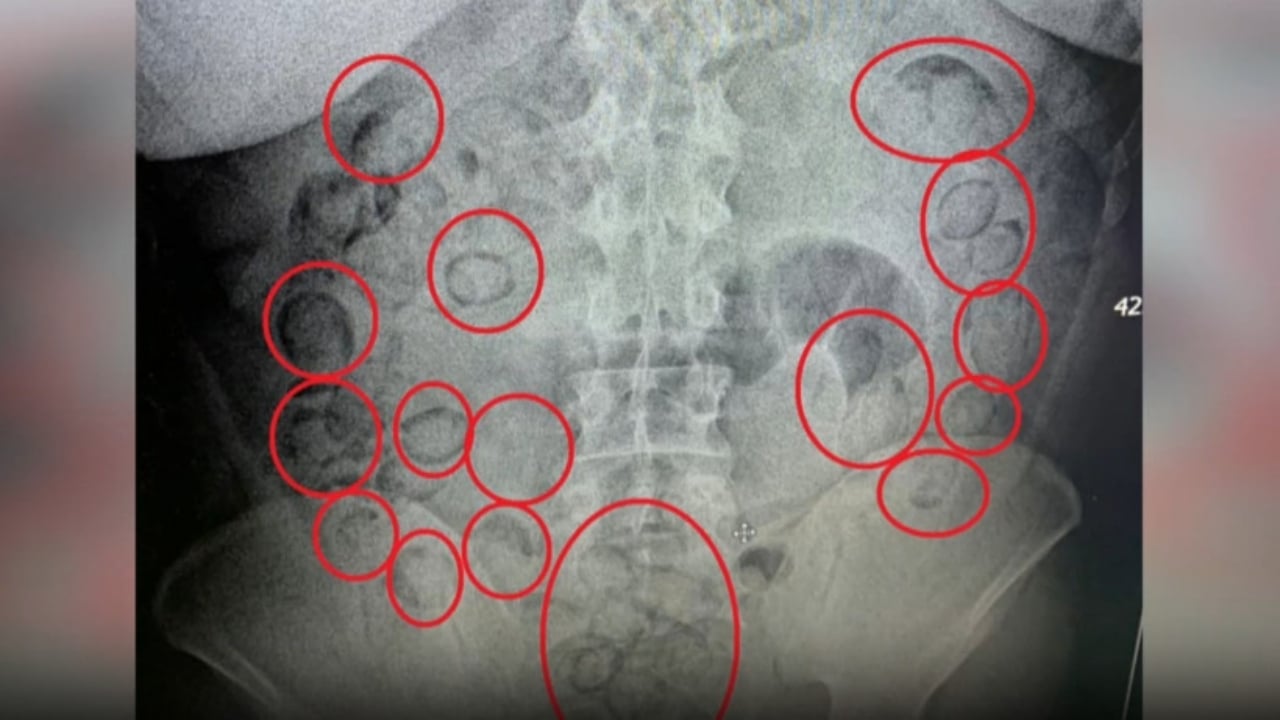

Aksaray'da polisin durdurduğu araçta şüpheli davranışlarda bulununca gözaltına alınan yabancı uyruklu A.M.'nin (20) yapılan muayenesinde midesinden 101 parça halinde 433 gram metamfetamin çıktı.

Araçta bulunan A.M. şüpheli davranışları nedeniyle gözaltına aldı. Aksaray Eğitim ve Araştırma Hastanesi'ne götürülen A.M.'nin çekilen röntgeninde midesinde uyuşturucu tespit edildi. Tıbbi müdahale ile A.M.'nin midesinden 101 parça halinde 433 gram metamfetamin çıkarıldı. Emniyetteki işlemlerinin ardından adliyeye sevk edilen A.M., çıkarıldığı mahkeme tarafından tutuklandı.